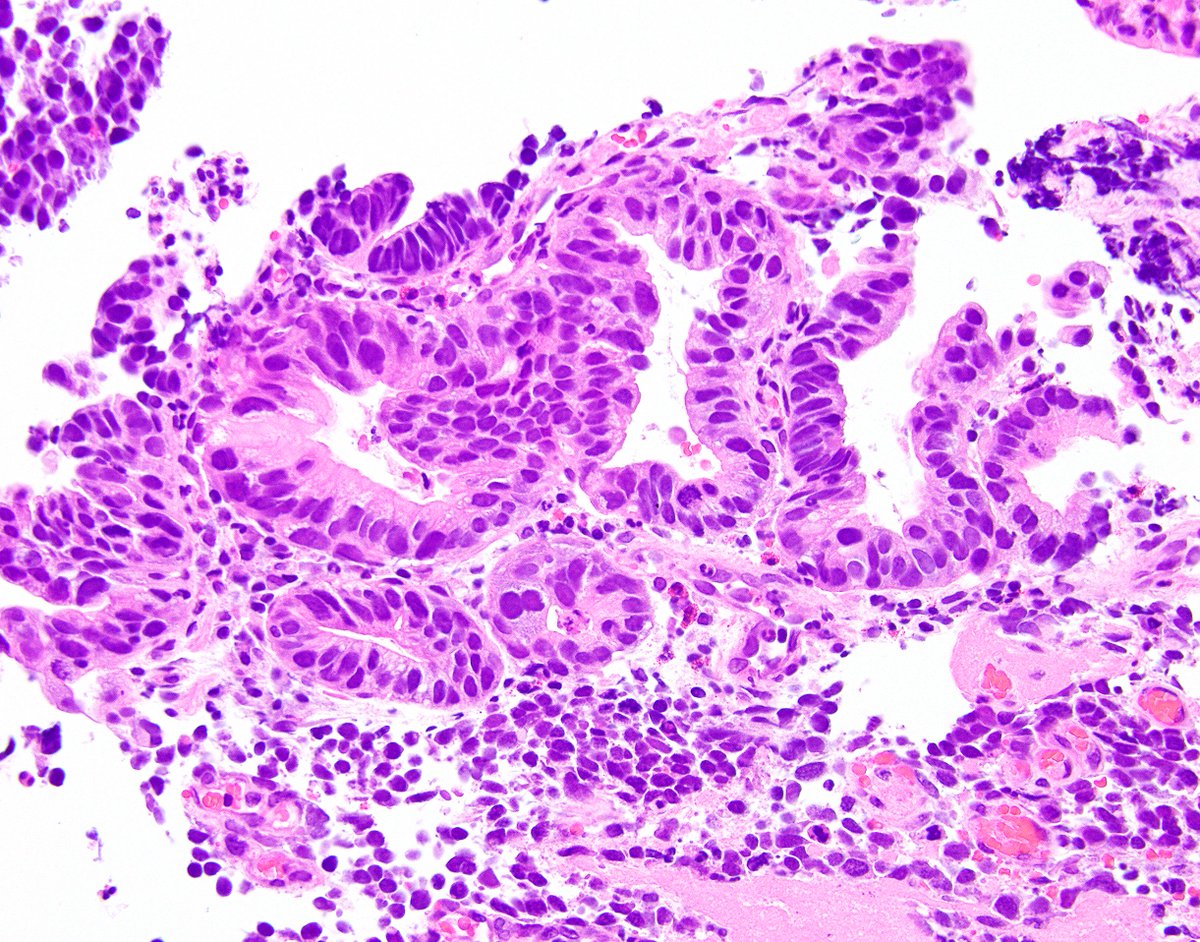

The tumor demonstrates large cell neuroendocrine carcinoma morphology. They tend to grow quickly and are more likely to spread. These cells divide at a low rate and therefore grow slowly.

Immunostains show the tumor is positive for synaptophysin and chromogranin, with a ki67 index of 85%. Large cell neuroendocrine cancer (lcnec) and small cell lung cancer (sclc) are high grade or poorly differentiated lung nets. The cancer is in the lung and is typically a few centimeters (cm) in size, but smaller than about 3 inches.

High grade neuroendocrine carcinoma. The mitotic index is more than 10, meaning that a large number of cells are dividing, and generally the tumor has outgrown its blood supply in many areas, which leads to necrosis. Reviewed prospectively maintained databases from two institutions of patients who underwent hepatic resection for neuroendocrine neoplasms between 1990 and 2006. The oral combination of capecitabine and temozolomide is considered a good option in the management of metastatic net g3 and may be preferred.